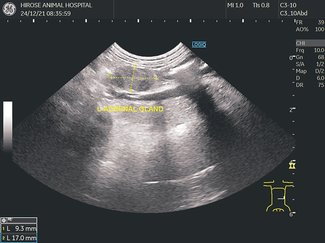

獣医のカルテ95雌鳥の卵詰まり/吉田動物病院(射水市小島)井出いづみ 2024年12月7日 05:00 ニュースプラン記事 文化・くらし 卵詰まり(卵塞(らんそく)症)は、おなかの中に卵があるのに産卵できない状態で、雌鳥の病気の中でも緊急性が高く、生命に危険を及ぼす可能性があるため早急な対応や治... 残り829文字(全文:909文字) この記事はニュースプラン記事です。 ログイン サービス詳細を見る ご案内 この記事を読むには北日本新聞パスの会員登録と以下のパックかプランの申し込みが必要です。 北日本新聞を定期購読している方、これから定期購読を希望する方は新聞購読コース 新聞ウェブパック(追加料金なし) 新聞プレミアムパック もっと詳しく webunプラスの利用だけをご希望の方はデジタルコース ニュースプラン プレミアムプラン もっと詳しく この機能は会員限定です。 お気に入りの記事を保存し、マイページで読むことができます。 ログイン 会員登録はこちら